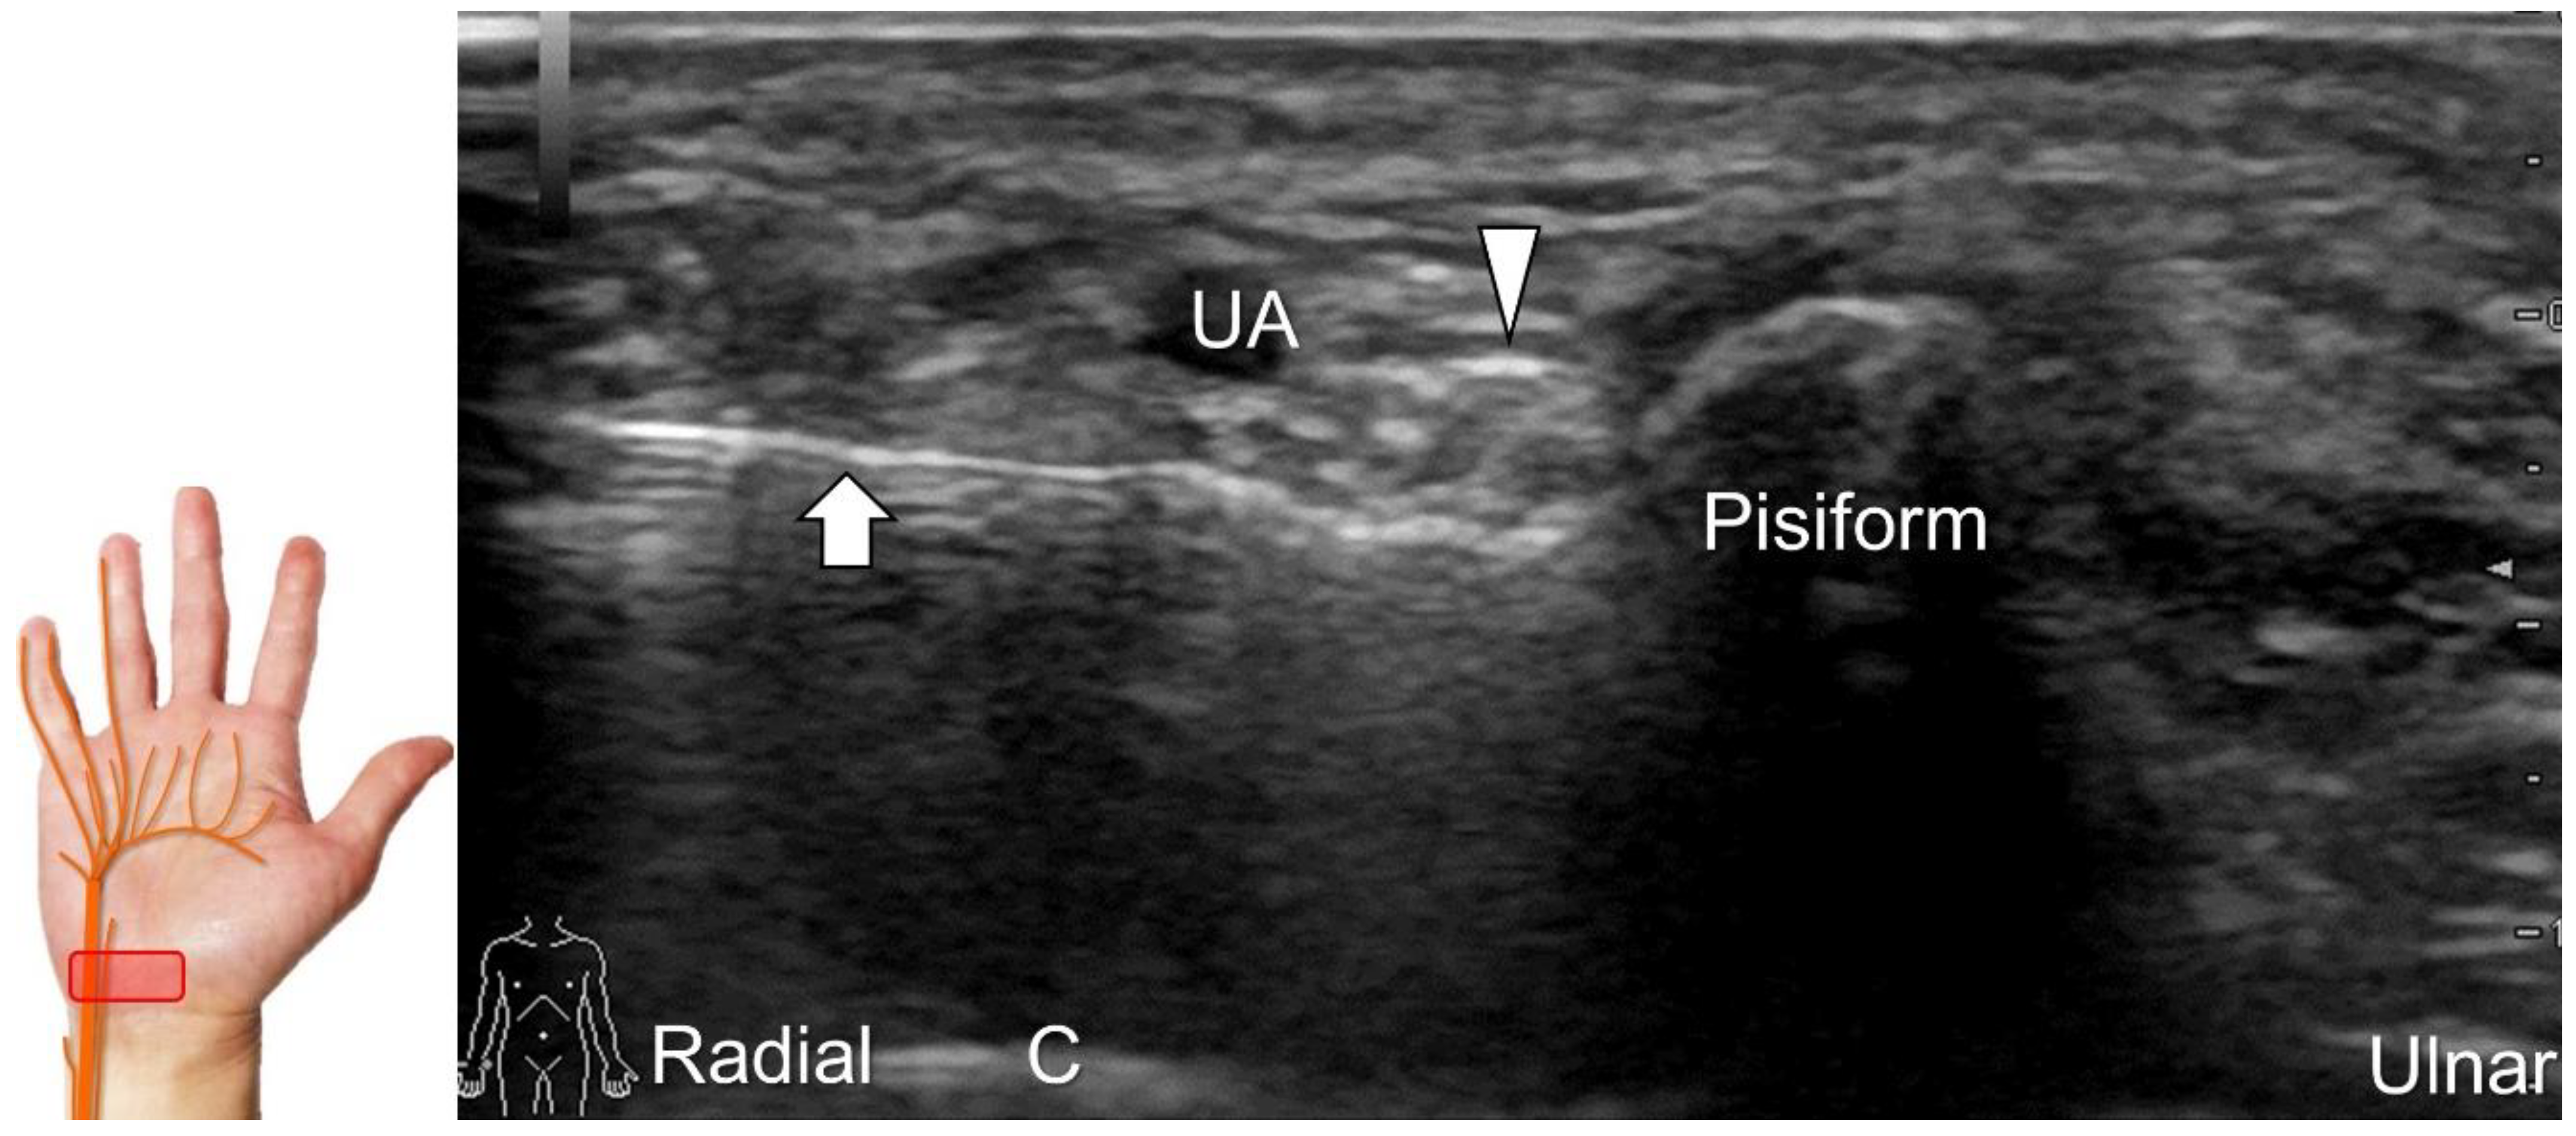

Scanning Technique

To locate the Guyon’s canal, the transducer is placed along the axial plane on the volar wrist with the forearm supinated. This will reveal the ulnar nerve and artery within the canal (Figure 13A). To investigate the nerve’s long axis, the transducer is rotated 90 degrees. By moving the transducer toward the finger, the superficial and deep branches can be seen. Between the pisiform and hamate, the superficial and deep branches (along with their accompanying vessels) can be visualized as separated by the fibrous arch of hypothenar muscles, respectively (Figure 13B) [39].

The superficial branch divides into two palmar digital nerves. They run superficially along the little finger and half of the ring finger. The deep branch, on the other hand, can be observed between the flexor digiti minimi brevis and opponens digiti minimi muscles before it penetrates the deep aspect of the palm (Figure 13C). By pivoting the transducer, the physician can display the long axis of the deep branch, extending all the way to the segment within the adductor pollicis muscle (Figure 13D).

Clinical Implication

Injuries to the ulnar nerve beyond the elbow can cause claw hand, which manifests as hyperextension at the metacarpophalangeal joints and flexion at the proximal and distal interphalangeal joints of the fourth and fifth fingers—due to the unopposed action of the ulnar side of the flexor digitorum profundus muscle against the paralyzed fourth and fifth lumbrical muscles. If the nerve injury is distal to the wrist crest, it can lead to Guyon’s canal syndrome or ulnar tunnel syndrome. To investigate such cases, the mean pooled cross-sectional area (CSA) of the ulnar nerve at the Guyon’s canal in healthy volunteers (4.1 mm2 with a 95% CI between 3.6 and 4.6 mm2) can be used as a reference [40].

Repeat contusions to the hypothenar region and space-occupying lesions such as ganglion cysts, fracture segments, spurs of the pisiform, schwannoma, ulnar artery thrombosis, or aneurysms and fibrolipomatus hamatoma (Figure 14) can cause Guyon’s canal syndrome. Compression at the inlet of the Guyon’s canal, which is located proximal to the bifurcation of the ulnar nerve into the superficial and deep branches, can result in both sensory and motor deficits. However, if the injury is located more distally (Figure 15A), e.g., due to a fracture of the hamate or pisohamate ligament sprain (Figure 15B,C), only motor deficits may be observed [38].

Handlebar neuropathy is a similar scenario that occurs due to continuous compression of the ulnar nerve at the ulnar wrist in cyclists. Focal swelling of the deep branch can be seen at the hamate level. An associated finding would be atrophy/weakness of the dorsal interossei muscles (Figure 16). For treatment, injection over the short axis of the ulnar nerve can be performed using the in-plane approach from the radial aspect in the Guyon’s canal (Figure 17). For certainty, identifying the ulnar artery is essential to prevent iatrogenic injury.

Figure 13. Sonographic imaging (short-axis view) shows the ulnar nerve within the Guyon’s canal (A), separation of branches beside the pisohamate hiatus (B), deep branch of the ulnar nerve located between the hypothenar muscles distal to the hook of the hamate (C). Long-axis view (through pivoting the transducer) shows the segment of the deep branch within the adductor pollicis muscle (D). Arrowhead: ulnar nerve; white arrows: superficial branch of the ulnar nerve; black arrows: deep branch of the ulnar nerve; orange arrow: branch of the ulnar nerve to the abductor digiti minimi; *: pisohamate ligment MN: median nerve; UA: ulnar artery; P: pisiform; H: hook of hamate; A: artery; L: lumbrical muscle; FDM: flexor digiti minimi brevis muscle; Opp DM: opponens digiti minimi muscle; AbDM: abductor digiti minimi muscle; AdP: adductor pollicis muscle.